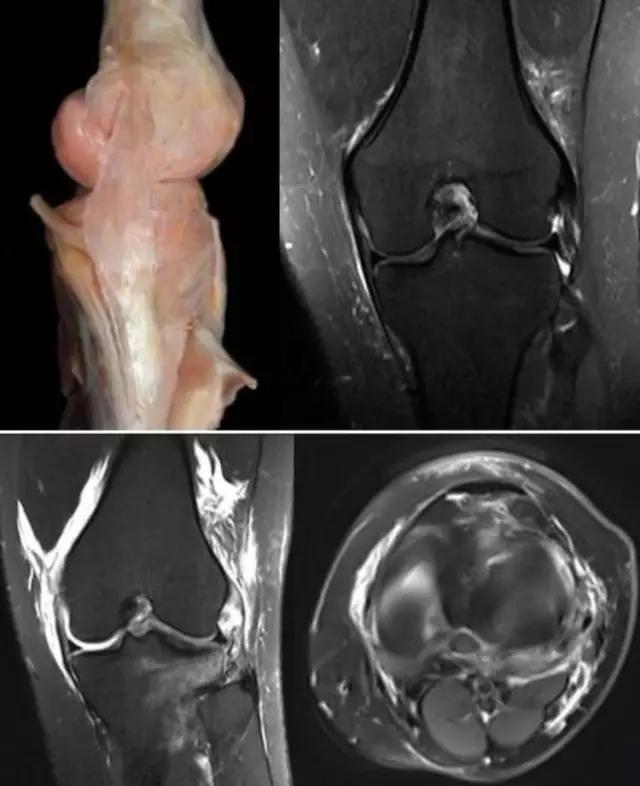

膝关节结核为侵袭性病变,会破坏膝关节的滑膜、软骨、骨等,所形成的寒性脓疡会顺着组织间隙流注,与其他疾病的表现不同。 病例:李XX,女,56岁,右膝关节疼痛逐渐加重8个月。手术及病理证实为膝关节结核。

利用临床检查——

临床检查更应该是临床医生的长处,密切结合临床检查阅片时才能有的放矢。 病例:吴XX,女,24岁,右膝关节内侧疼痛不能触摸5年。曾在多家医院局部封闭等治疗。查体:右膝关节外观无明显变化,屈伸好,膝关节前内下方有固定的压痛点,不给用力压迫。 MRI:膝关节内无明显改变,临床检查压痛部位有小范围高信号,中央有混杂信号。(诊断报告正常) 考虑:膝关节血管瘤。

该患者手术时肉眼所见及术后病理确诊为血管瘤。